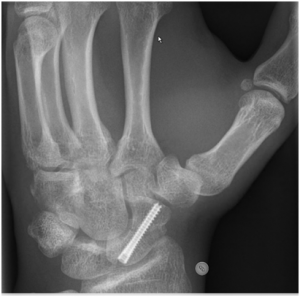

More explosive loads can result in injury to the scapholunate ligament complex which plays an important role in wrist stability. It’s the wrist equivalent of the ACL ligament of the knee and if injured instability and pain can result. High grade scapholunate tears are generally more serious.